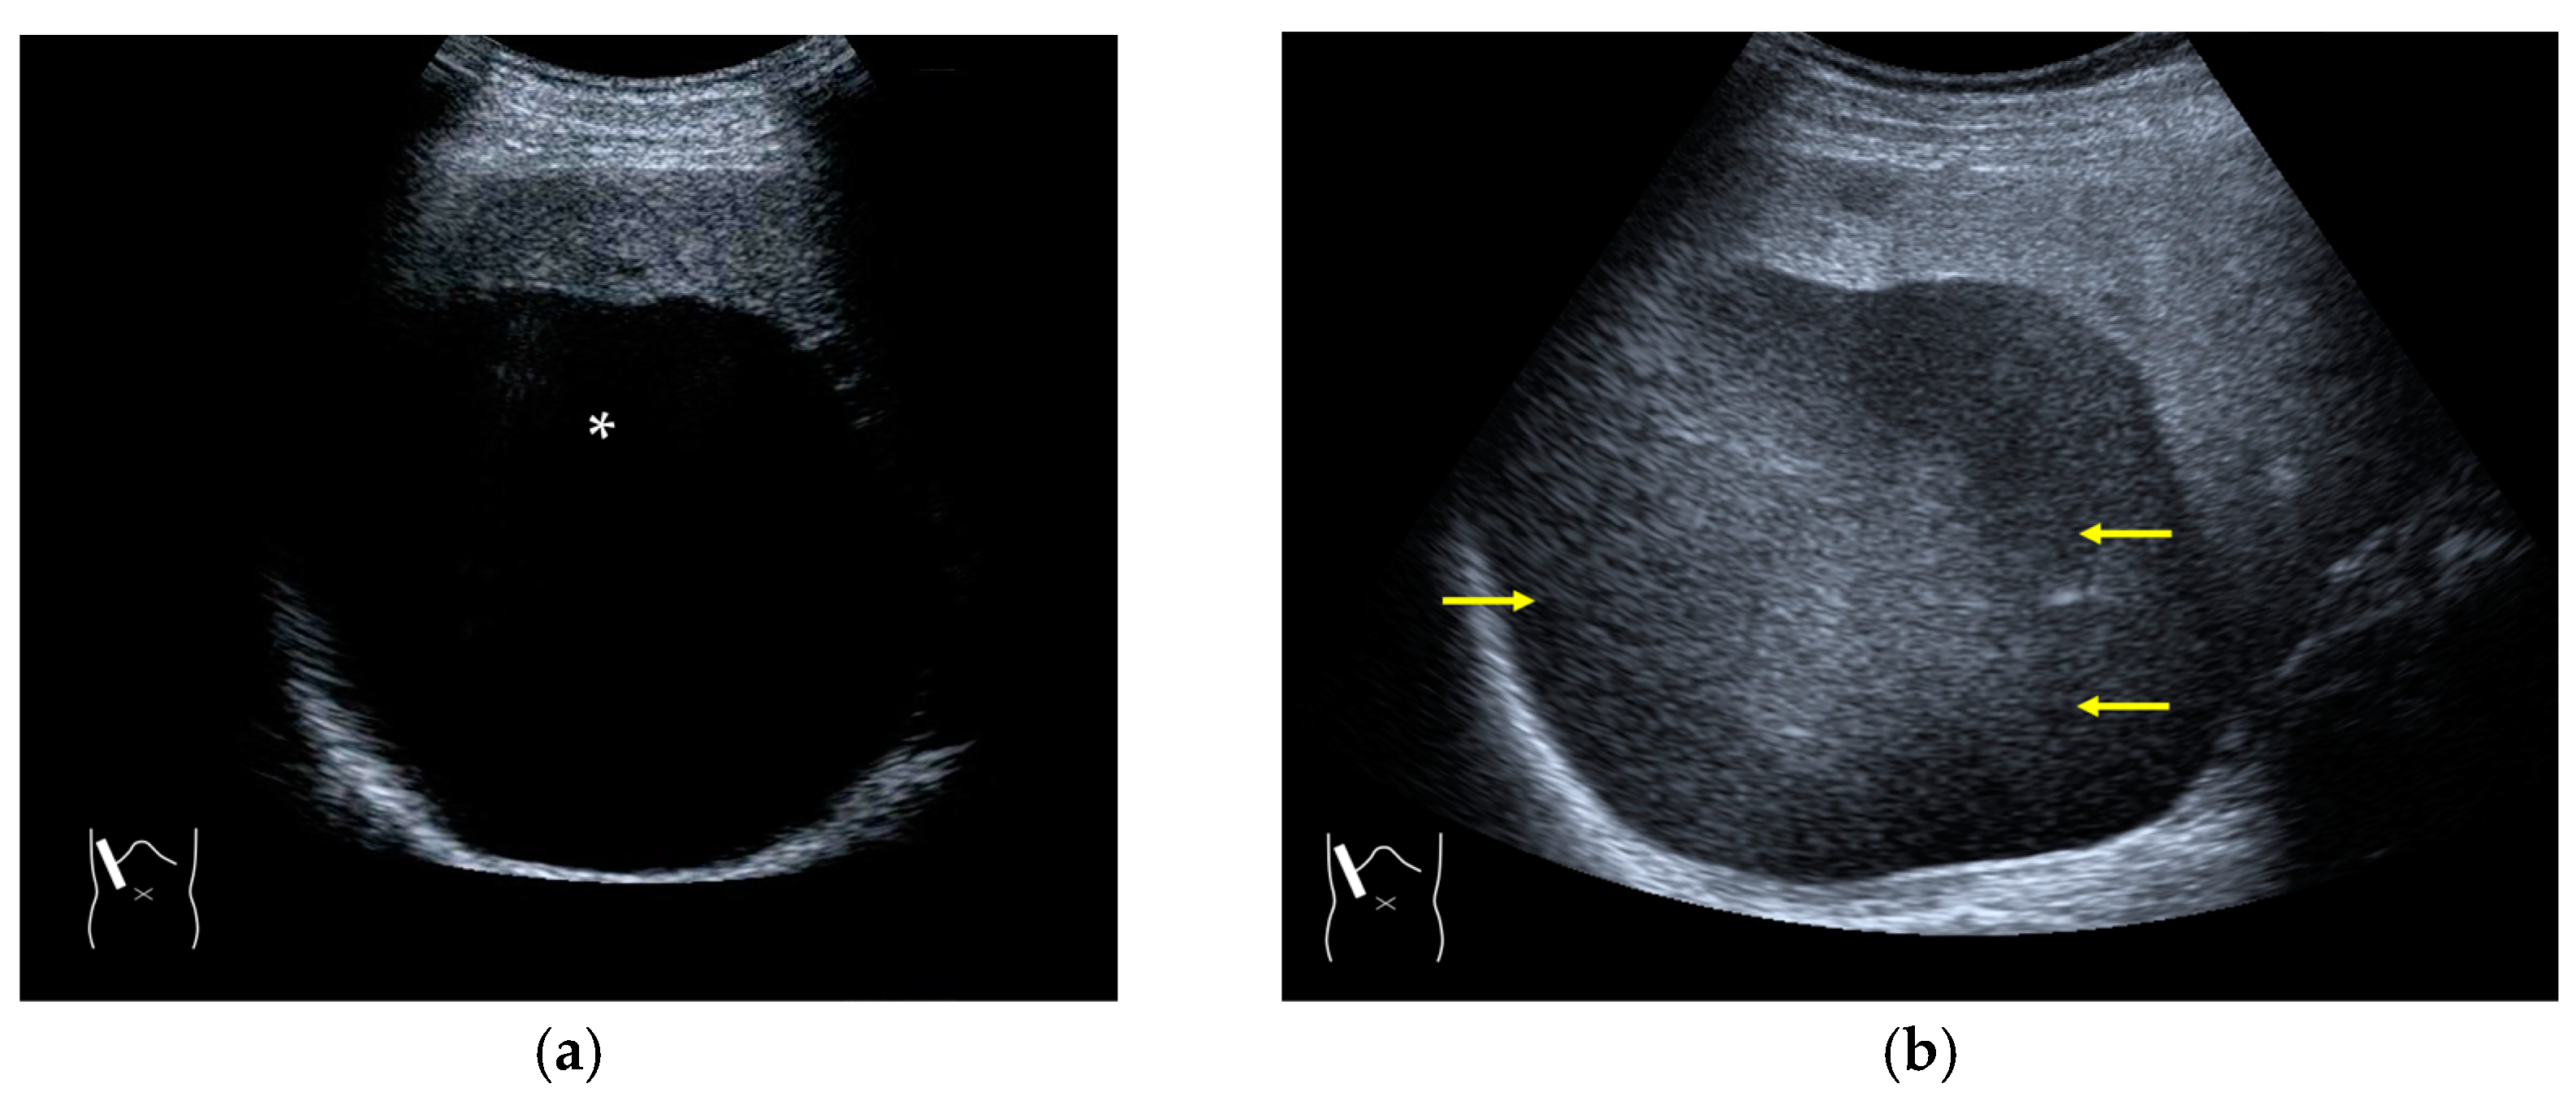

3.1.3. Range-Ambiguity Artifacts (RAAs)

RAAs have recently attracted increased attention due to their increasing appearance when using recent high-end US equipment [42,43]. Although most operators encounter these artifacts in daily US examinations, they sometimes possess insufficient knowledge and feel diagnostic confusion with real structures, which is mainly because RAAs have seldom been described in the literature [42,43]. These artifacts are slightly more complex than the other B-mode artifacts. The composition of B-mode US images is based on the following assumptions: (i) the US beam passes along the same line path from the transducer to the target and back to the transducer and (ii) all received echoes come from the most recently transmitted pulse. Explaining the emission/reception of a pulse forms the basis for understanding RAAs. Assumption (ii) inevitably causes the following phenomenon: structures below the scanning depth appear in the US image when the echoes from deep structures detected with the first pulse return to the transducer after the second pulse has been emitted. The echoes coming from deep structures are, consequently, misinterpreted as having originated from the second pulse and are improperly displayed near the transducer (Figure 10). The easiest diagnostic strategy is to change the depth of the US image because this automatically changes the pulse repetition frequency (PRF) 4) [42,43].

Figure 10.

Range-ambiguity artifact in a hepatic cyst. (a) CEUS reveals a non-enhanced cyst (*) before the injection of the contrast medium. (b) Cloud-like echo (range-ambiguity artifact: RAA) appears in this hepatic cyst (arrows). (c) RAA disappears by changing the maximal depth of the view field. (d) Mechanism of RAA. When the PRF is high, the echo from the deep area is received during the second pulse’s receiving period and erroneously displayed closer to the transducer.